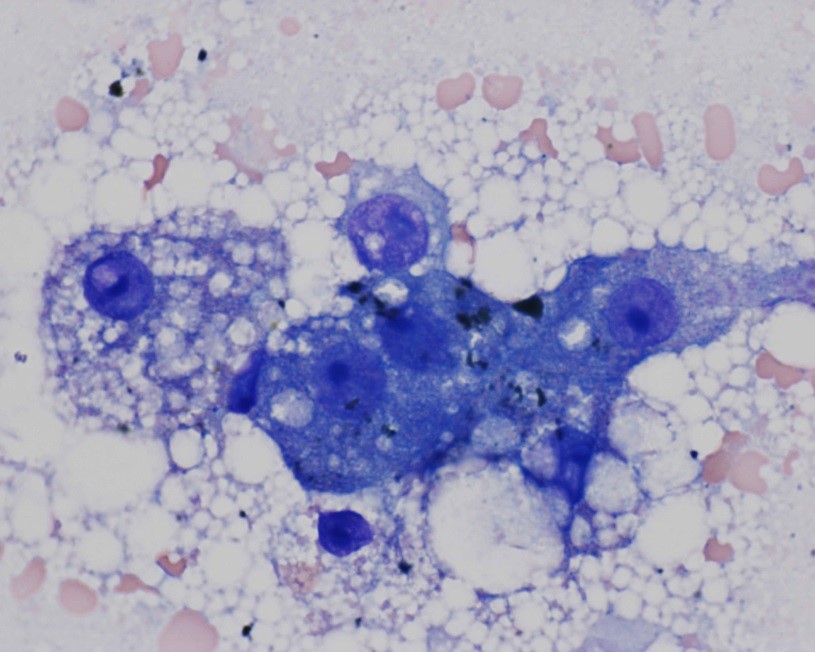

Cytology of fine-needle liver biopsy: Highly cellular sample contains hepatocytes with marked vacuolation and extracellular bile casts.

High Power view